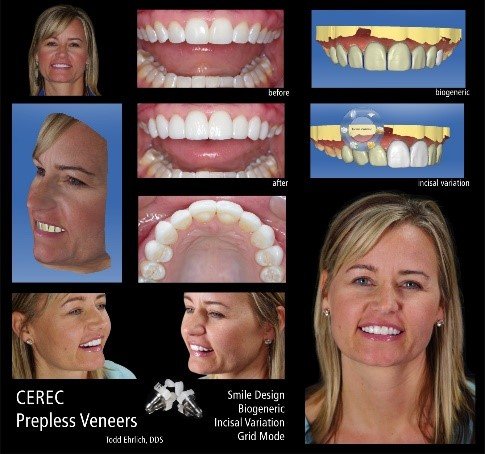

Case Study 2: Digital Workflow for Porcelain Veneers

Patient Profile:

- 42-year-old male

- Chief complaint: “I want to close my gap and improve the color of my teeth”

- 2.5mm midline diastema with mild tetracycline staining

- Previous orthodontic treatment with relapse

- Moderate incisal wear from bruxism

Diagnostic Process:

- Comprehensive digital records:

- Full-face and intraoral photographs

- Intraoral scan (iTero Element 5D)

- Digital smile design analysis

- T-Scan occlusal analysis

- Digital treatment planning:

- 3D virtual wax-up

- Preparation depth analysis

- Material selection simulation

- Occlusal scheme verification

Treatment Protocol:

- Minimally invasive preparation guided by 3D-printed reduction guide:

- 0.3mm facial reduction

- 0.5mm incisal reduction

- Supragingival margin placement

- Digital impression and provisional phase:

- Immediate provisionals milled from pre-approved design

- Two-week functional and aesthetic assessment period

- Final restoration fabrication:

- Material selected: lithium disilicate (IPS e.max)

- Staining and glazing for enhanced characterization

- Thickness: 0.5mm facial, 1.0mm incisal

- Adhesive cementation protocol:

- Try-in with glycerin-based paste

- 5% hydrofluoric acid etch (20 seconds)

- Silane application (60 seconds)

- Adhesive resin application (no light cure)

- Light-cured resin cement (A1 shade)

Three-Year Follow-up:

- Complete diastema closure maintained

- No ceramic fractures

- Minor occlusal adjustment needed at 2-year recall

- Excellent margin integrity and color stability

CEREC Smile Design   | Dentsply Sirona | Chairside integration, immediate visualization | CEREC ecosystem | Easy | Included with CEREC |